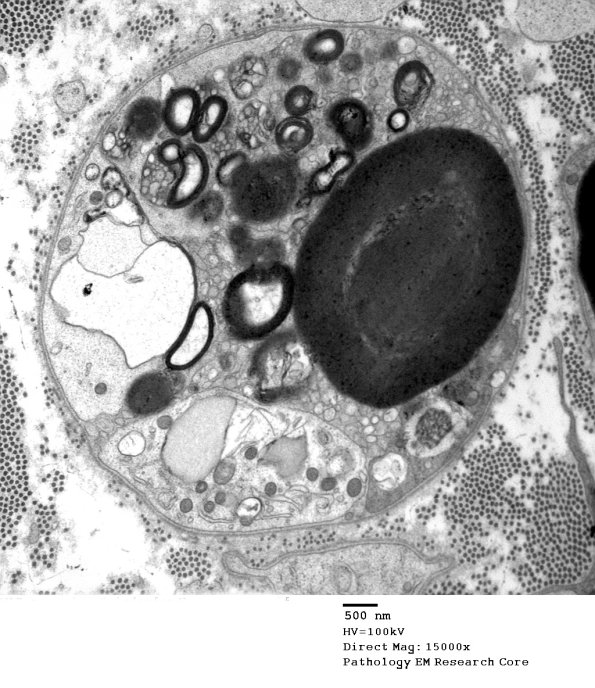

The endoneurium was rich in actively degenerating axons. (electron micrographs) ---- Comment: The findings of subperineurial edema, focal subperineurial hemorrhage, and microvascular endothelial changes suggest that an immune disorder affecting blood vessels – without classic vasculitis (fibrinoid necrosis) – may have played a role.